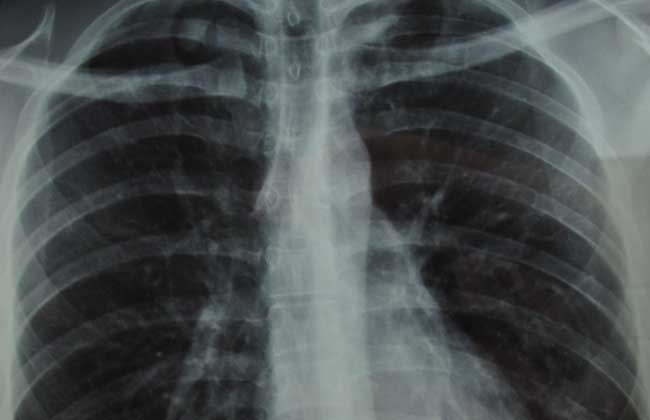

胸膜炎可传染,几率因病症而异。因为细菌主要通过呼吸道传播与传染。当排菌的胸膜炎病人咳嗽、打喷嚏、大声说话时,大量含有细菌的微小痰沫排放至空气中,然后被健康人吸入。健康人受到细菌感染后是否发生胸膜炎疾病,还要看两种因素的综合作用,即受到感染细菌毒力的大小和身体抵抗力的高低。当细菌毒力强,且身体抵抗力低时,就容易发生胸膜炎病,发生几率在10%左右。